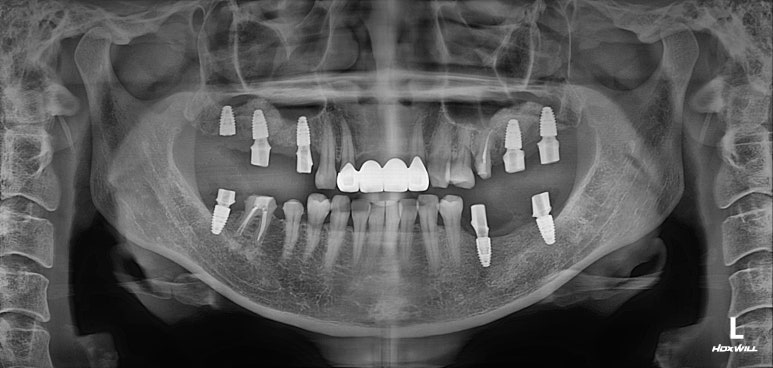

그렇게해서 최종완료 후 치과용 파노라마 사진입니다!

치과치료에 대해 잘 모르시는 분이라 할지라도 보고 있으면, 치료가 조화롭게 잘 끝났구나.. 라고 아실 수 있으리라 생각합니다.

제가 제일 좋아하는 치과용 파노라마 비교 사진입니다.

앞으로 나란히를 한 것 같이 평행한 임플란트의 완성도는 항상 카타르시스를 느끼게 합니다.

정말 어디하나 나무랄 것 없이 치료가 잘 마무리되었는데, 물론 정말 열심히 정성들여 수술하는 저도 칭찬받아야 마땅하지만 늘 묵묵히 열심히 크라운 치료를 잘 해주는 우리 보철과 전문의 원장님들께 그 공을 돌리고 싶습니다.

마지막에 심었던 오른쪽 위 어금니 임플란트 골유착이 완성되었고, 그동안 나머지 부위들은 임플란트 크라운 치료를 완료 해두었습니다.

상당히 깔끔하게 제작되었고, 기존에 해둔 상악동 뼈이식술도 아주 잘 자리잡아주었네요.

3개월의 치유기간이 늘어 힘들 수도 있었지만, 치료를 잘 따라와주신 환자분께 감사의 말씀 전합니다.